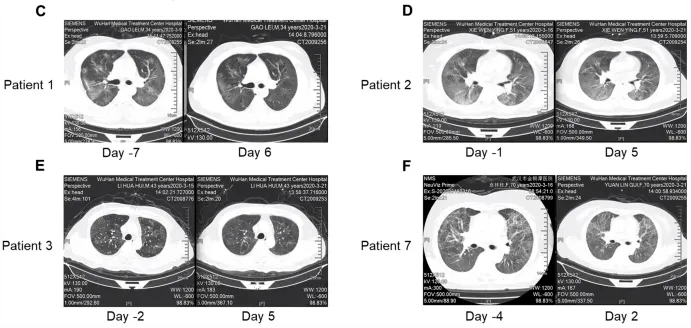

所有(yǒu)患者在氣溶膠吸入haMSC-Exos後肺部病變不( ₽bù)同程度的(de)消退,其中一(yī)位70歲© 女(nǚ)性患者的(de)肺部影(yǐng☆©δ¶)像改善最為(wèi)明(míng)顯,也₩♦•(yě)有(yǒu)患者出現(xiàn)浸潤和(hé)磨玻"↕↕↓璃影(yǐng)消失(見(jiàn)下(xià)圖→←✔)。患者吸入haMSC-Exos前後胸部 CT 掃¥♥描的(de)變化(huà)